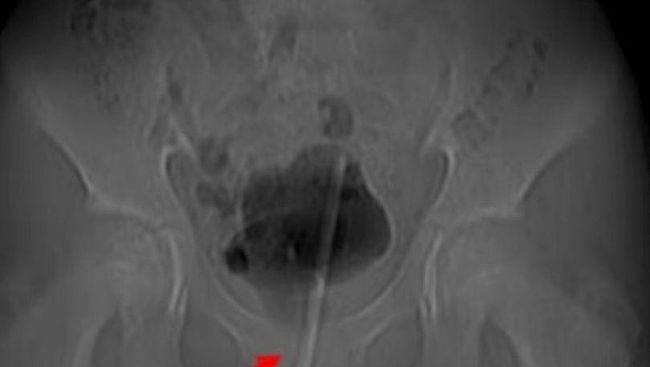

Termometer masuk ke dalam penis remaja laki-laki. (Foto: Asian Journal of Surgery)

Setelah discan menggunakan x-ray, termometer tersangkut ke dalam kandung kemih melalui saluran kemihnya. Dokter memilih mengangkat termometer itu menggunakan operasi lubang kunci.

Operasi ini dijelaskan lebih rinci oleh ahli urologi dalam jurnal Asian Journal of Surgery. Para peneliti mengatakan, mereka membuat lubang bedah kecil di jaringan ke kandung kemih, kemudian menggunakan alat kecil untuk menggerakkan termometer ke posisi yang benar untuk mencabutnya.